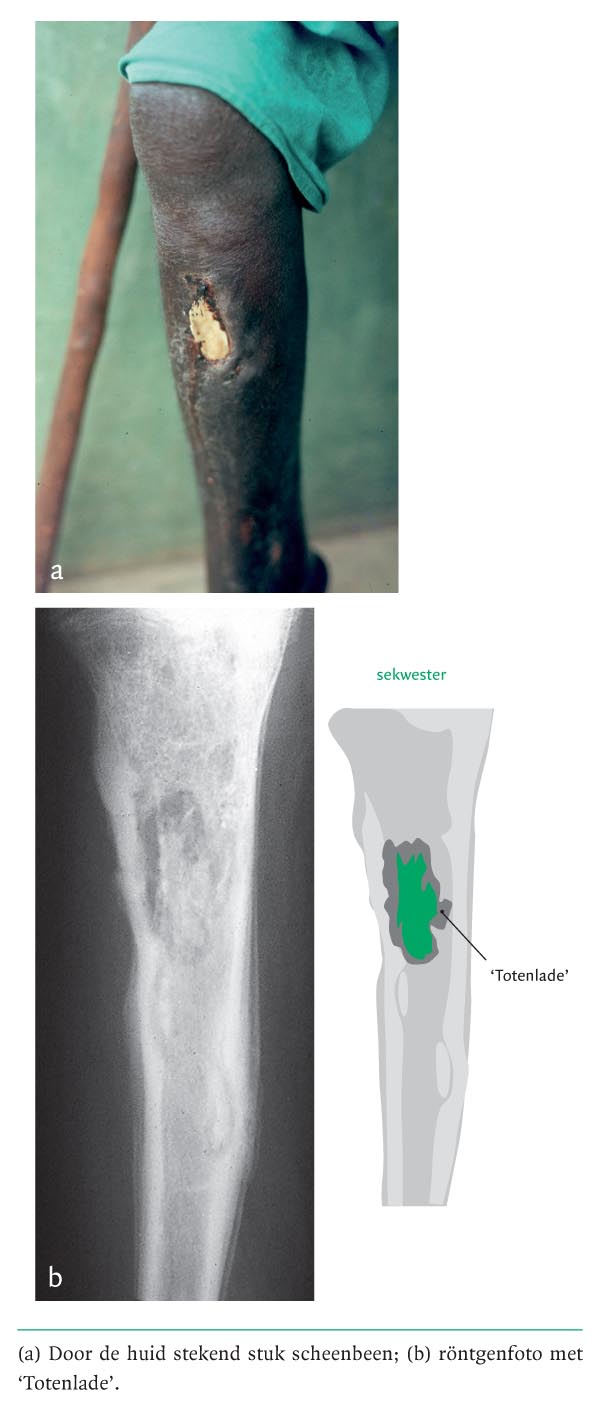

Diagnose in beeld (301). Een man met een uitstekend stuk scheenbeen

Een 55-jarige man werd gezien op de polikliniek van een ruraal ziekenhuis in Afrika. Hij had al jaren last van een pussende wond op het rechter scheenbeen. Geleidelijk was er een verharding opgetreden en uiteindelijk was er duidelijk bot van buitenaf waarneembaar (figuur a). Op de röntgenfoto waren een groot sekwester en osteomyelitis te zien (zie figuur b). Het sekwester was voor twee derde gelegen in een nieuwgevormd kapsel van beenweefsel, een zogenaamde ‘Totenlade’. Het andere deel van het sekwester perforeerde de huid. Het sekwester zat stevig vast, maar kon in stukken verwijderd worden. Na een…